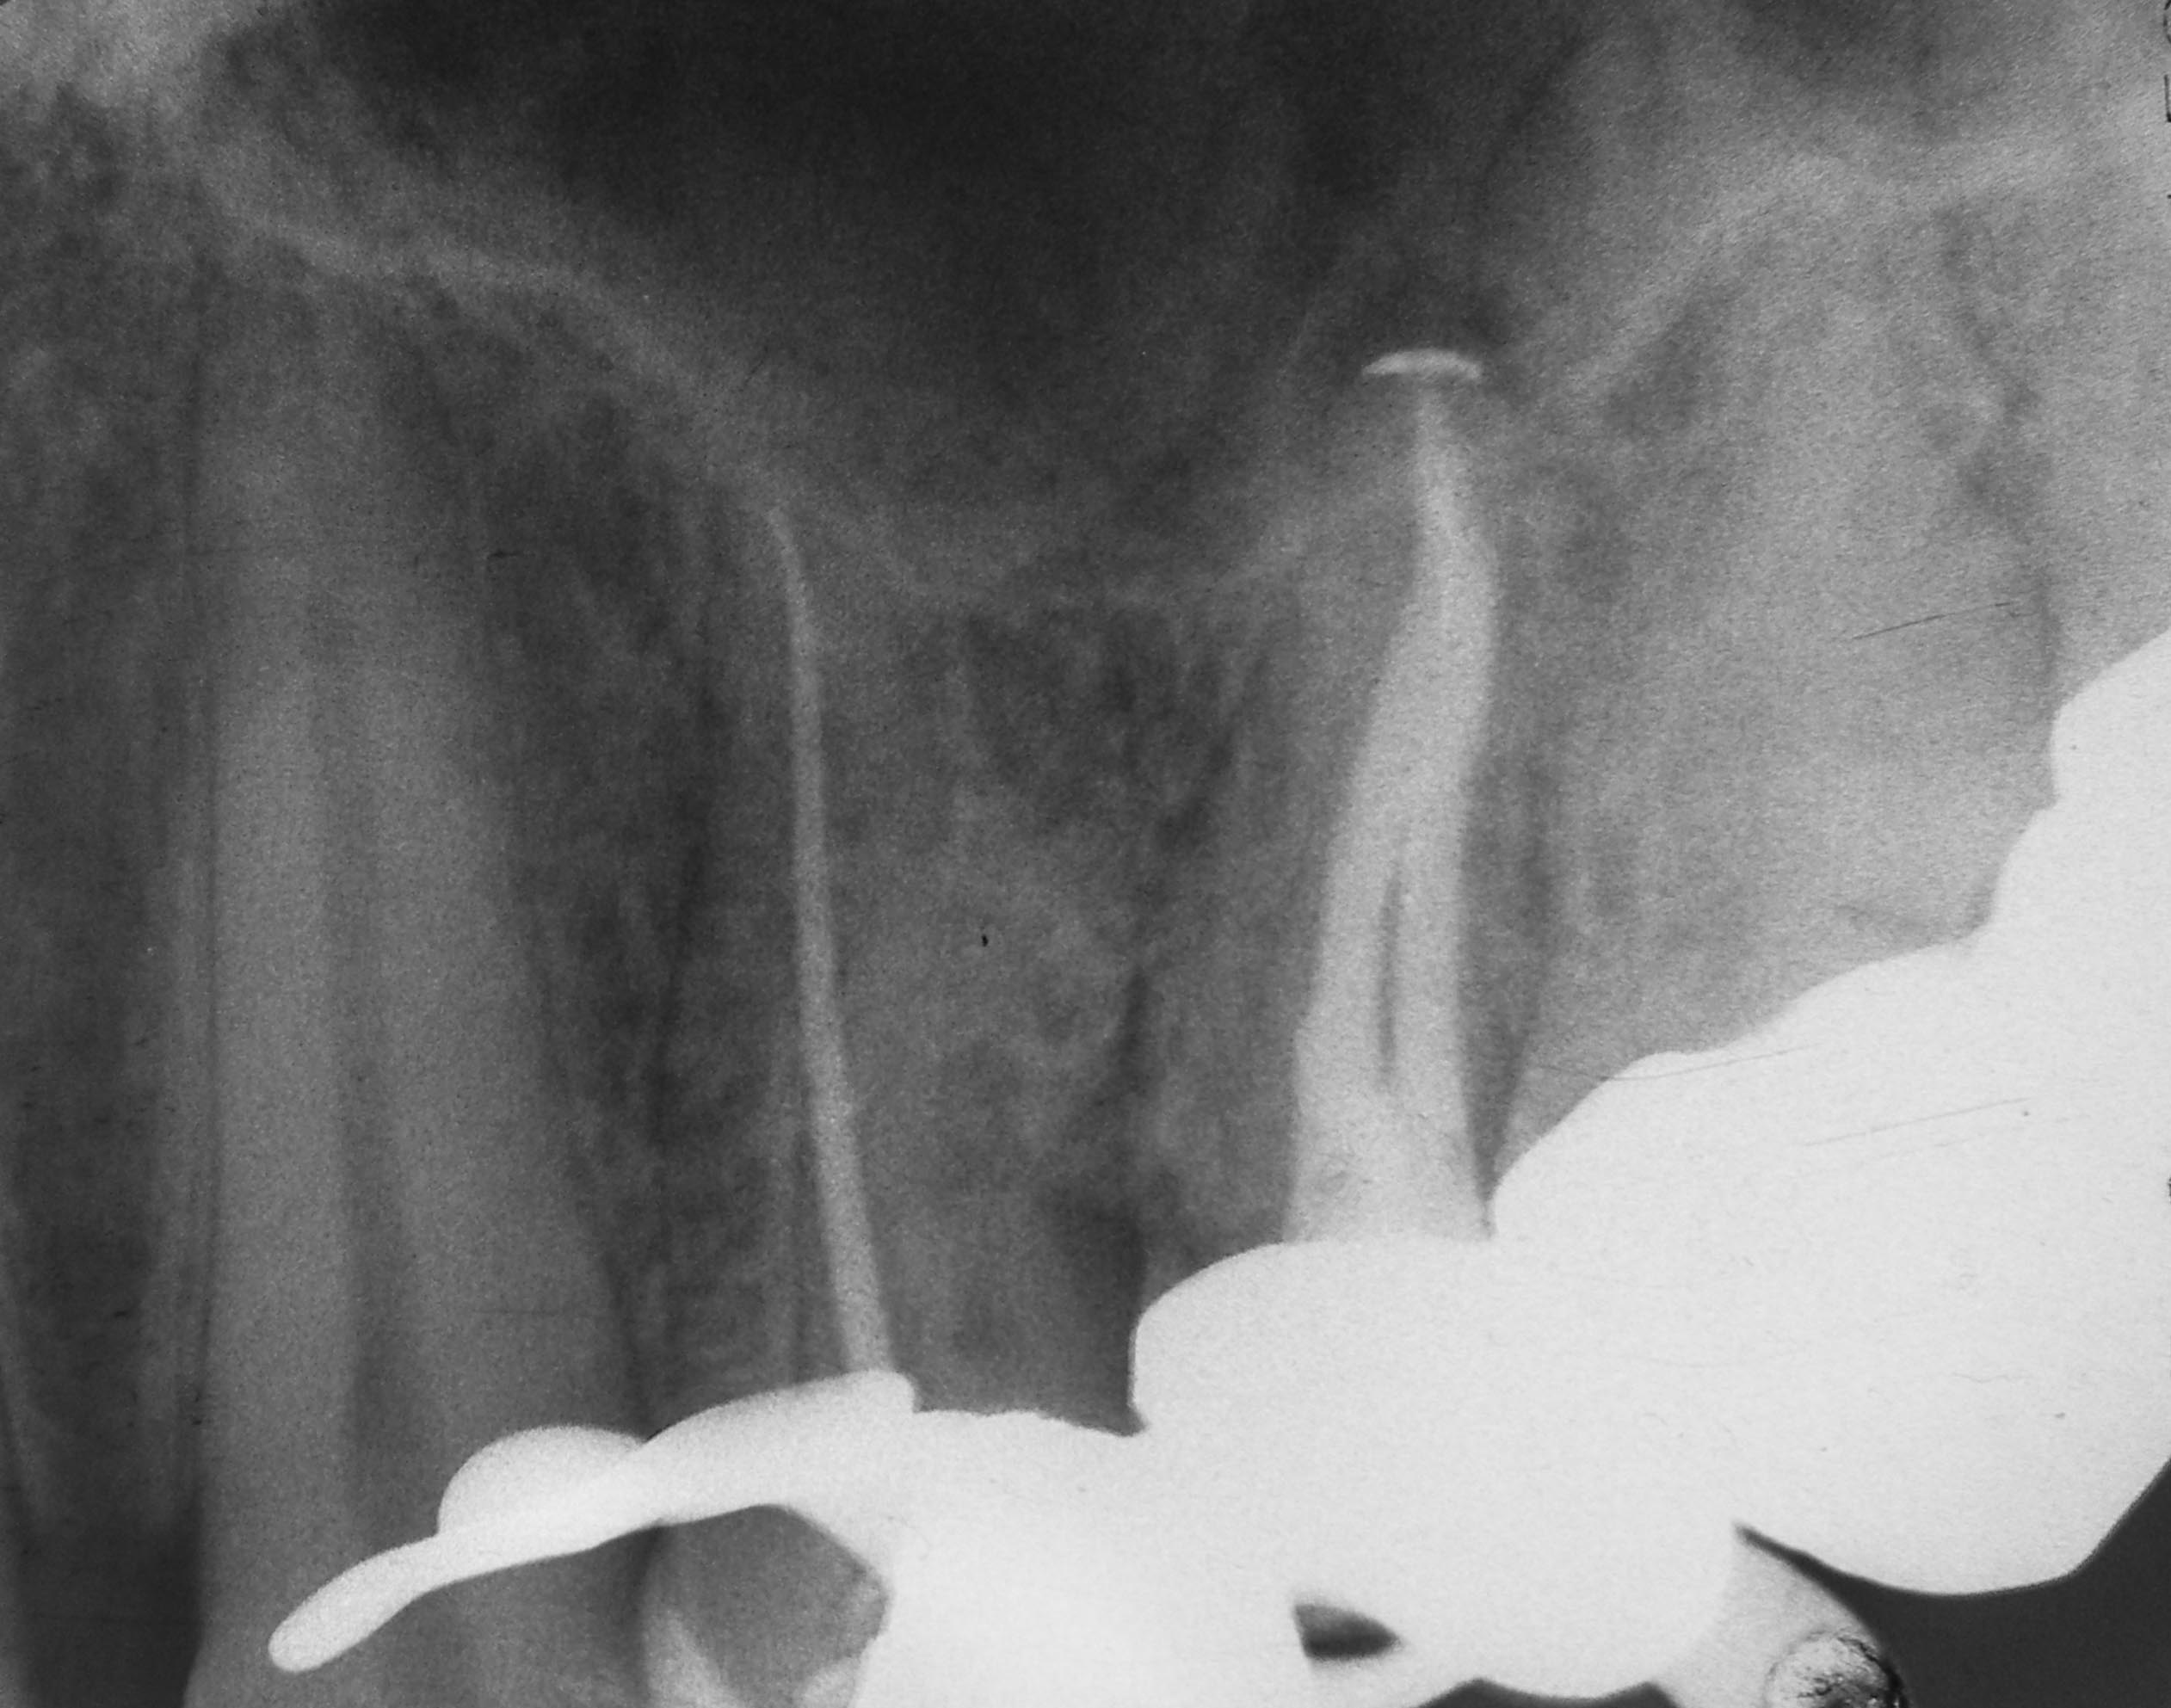

24 Masterpoint lingualer Kanal Veröffentlicht 4. November 2013 am 2523 × 1985 in „Chapeau“ oder der Wirt und die Wette 24 Masterpoint lingualer Kanal